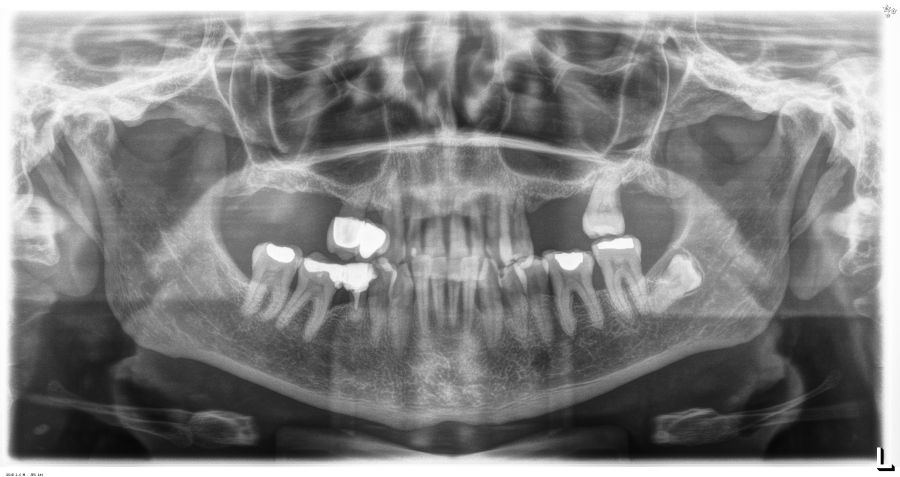

Presentamos el caso de una paciente femenina de 56 años de edad que acude a la consulta demandando un tratamiento con implantes dentales para reponer los dientes ausentes en ambos sectores posteriores maxilares. En ambos cuadrantes superiores, los molares se perdieron hace varios años. La paciente no se ha realizado la reposición de los mismos hasta ahora, ya que en otros centros consultados la propuesta terapéutica fue la de realizar injertos y regeneración ósea para poder ganar volumen óseo suficiente antes de colocar los implantes. La paciente busca otras alternativas menos invasivas y por ello acude a la visita. En las imágenes intraorales se observa la falta de los molares en los sectores posteriores maxilares con excepción del 27, que actualmente tiene un compromiso periodontal importante (Figuras 1-4). El resto de dientes también se encuentran afectados por una enfermedad periodontal avanzada con pérdida ósea horizontal (Figura 5).